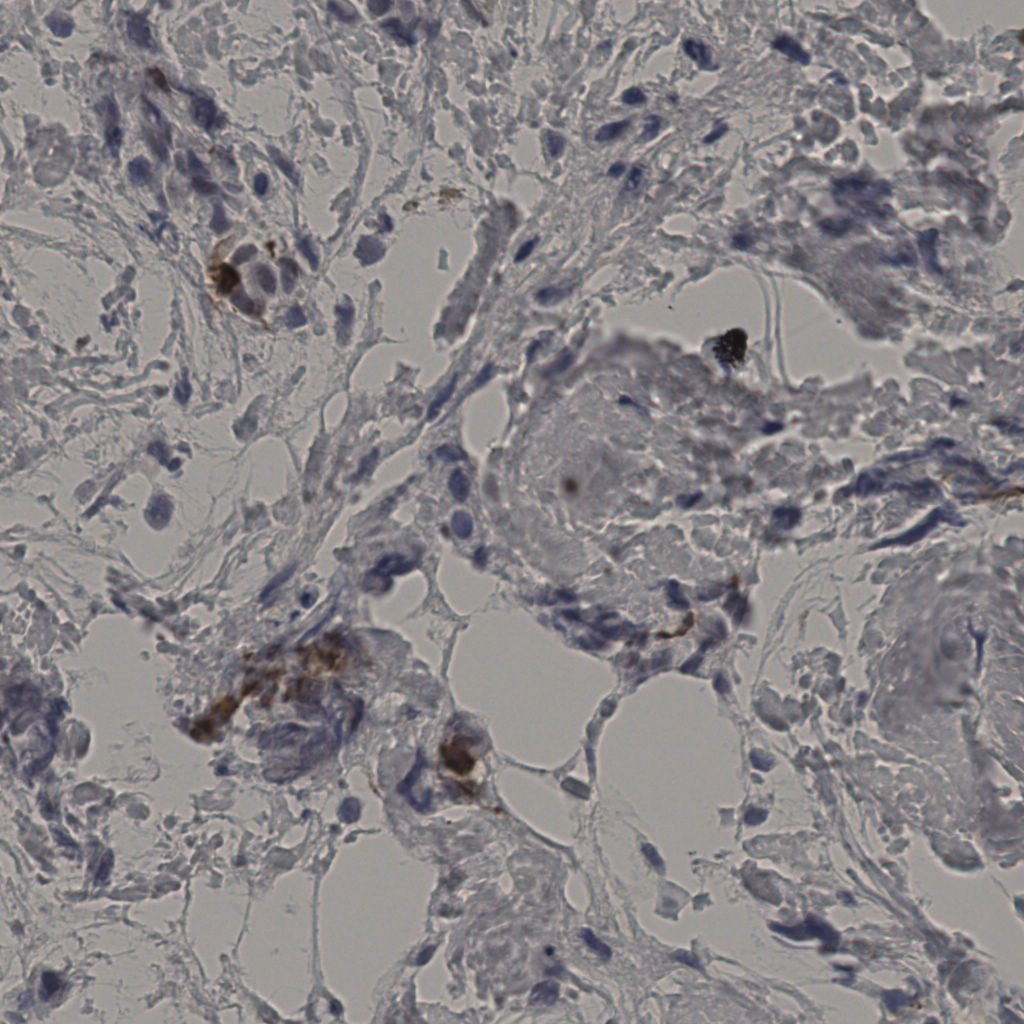

slice_32_21_x2867...

slice_32_22_x2867...

slice_32_23_x2867...

slice_32_24_x2867...

slice_32_25_x2867...

slice_32_30_x2867...

slice_32_31_x2867...

slice_32_32_x2867...

slice_32_33_x2867...

slice_32_34_x2867...

slice_32_35_x2867...

slice_32_4_x28672...

slice_32_5_x28672...